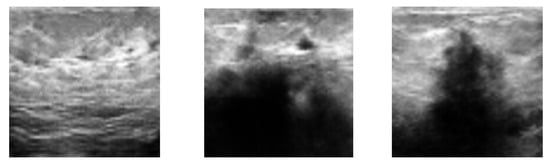

Augmentation of Small Ultrasound Databases: A Practical Approach

by Onsasipat Kasamrach, Thiansiri Luangwilai and Stanislav Makhanov

Mathematics 2026, 14(4), 646; https://doi.org/10.3390/math14040646 - 12 Feb 2026

Generative Adversarial Networks (GANs) have emerged as a promising tool for augmenting medical image datasets used by AI solutions. However, GANs trained on small datasets (300–500 images) frequently encounter mode collapse, overfitting, and instability, which hinder their practical application. Many GAN-generated images look unrealistic. The Enhanced Deep Convolutional GAN (EDCGAN) is introduced to generate high-quality synthetic images of breast US (BUS). The model includes an experimental design for the Discriminator and Generator. The main components are spectral normalization (SN), the Squeeze-and-Excitation (SE) block, and the Scaled Exponential Linear Unit (SELU). One of the basic versions of DCGAN is considered for the proposed modifications. The stopping criteria are based on the convergence of the smoothed loss function and the constraints imposed on the Discriminator. The contribution is a combination of the above modifications and postprocessing based on the visual evaluation by radiologists and selected image processing metrics. The Inception Score (IS), the Structural Similarity Index (SSIM), and the Mean Squared Error (MSE) comply with the results obtained in the preceding works. The efficiency of augmenting the US data has been verified on a DL classification based on ResNet-18. The tests against training on a non-augmented data outperform ResNet by 5% and by the data augmented by the previous DCGAN by 3%. These numbers are substantial since this variant of ResNet has been pre-trained on 1000 categories by ImageNet-1K, including 1.28 million images. Additionally, the model wins the “Guess-the-real-image” game, competing with seven preceding GANs. Full article